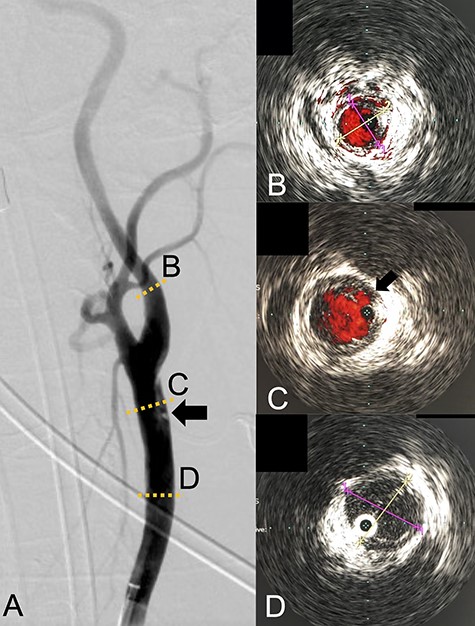

We performed CAS and started dual antiplatelet therapy 27 days after stroke onset to prevent further dissection and cerebral infarction recurrence. The dissection started 1.5-cm below the carotid bifurcation (Fig. 3A). An 8 fr guiding catheter (FlowGate2 Balloon Guide Catheter, Stryker, Fremont, CA, USA) was positioned at the proximal portion of the left CCA with a micro-guidewire (ASAHI CHIKAI Black, Asahi-Intecc, Nagoya, Aichi, Japan) crossing the dissected lesion. A distal protection device (SpiderFx Embolic Protection Device, Medtronic, Minneapolis, MN, USA) was deployed at the petrous portion of the ICA. IVUS was first advanced into the petrous ICA, and vessel wall imaging was performed by slowly withdrawing the device. IVUS imaging confirmed the existence of the dissection’s pseudo-lumen starting 1-cm proximal to the carotid bifurcation (Fig. 3C). IVUS provided the ICA and CCA diameters, which helped decide the most suitable stent (Fig. 3B and C). To adequately cover the dissection lesion, we placed two opened cell stents (Protégé, Medtronic, Minneapolis, MN, USA); one was an 8–6-mm tapered model with a length of 40 mm to cover the lesion from the distal CCA end to the proximal portion of ICA. Another was a 10-mm straight model with a length of 40 mm covering the CCA. Post-dilation was performed SterlingTM Balloon Dilation Catheter (Boston Scientific, Natick, MA, USA) with 5 × 20 mm covering both stents’ edges. The final angiography showed successful treatment with a smooth intra-arterial lumen (Fig. 4A). IVUS imaging showed sufficient stent coverage of the entire dissection lesion. It also confirmed a good expansion of the stent to the dissection area’s arterial wall with no plaque protruding the stents (Fig. 4B).

Angiography revealed the dissection starting proximal to the carotid bifurcation (Black arrow: A). IVUS provided the diameters of the ICA and CCA (B and D, respectively). IVUS imaging confirmed the pseudo-lumen of the dissection starting 1-cm proximal to carotid bifurcation (C) and the entry point of the dissection as well (Black arrow: C).